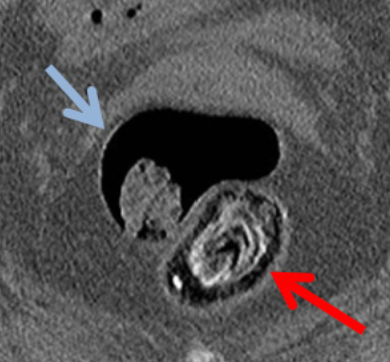

Tamara Viñas Martínez, Paola Melgar Requena, Jose Manuel Ramia Angel

|

|

|